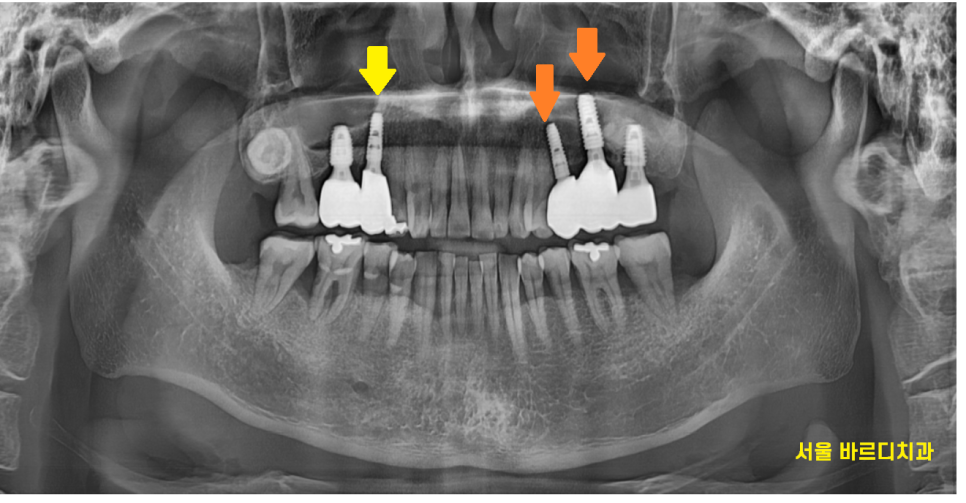

240729

임플란트 완성한 모습입니다.

잇몸 내려감으로 뼈가 꺼져있었기에

회복에 집중했습니다.

부족한 부분은 뼈이식을 통해 보충

원상태로 복귀시켜드렸습니다.